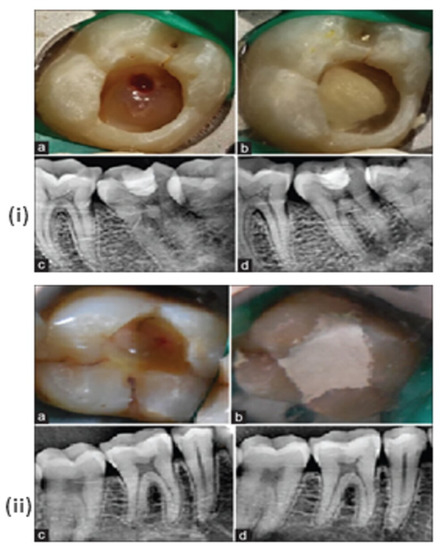

- Hegde, S.; Sowmya, B.; Mathew, S.; Bhandi, S.; Nagaraja, S.; Dinesh, K. Clinical evaluation of mineral trioxide aggregate and biodentine as direct pulp capping agents in carious teeth. J. Conserv. Dent. 2017, 20, 91–95. [Google Scholar] [CrossRef]

- Parirokh, M.; Torabinejad, M.; Dummer, P. Mineral trioxide aggregate and other bioactive endodontic cements: An updated overview—Part I: Vital pulp therapy. Int. Endod. J. 2018, 51, 177–205. [Google Scholar] [CrossRef] [PubMed]

- Guagnano, R.; Romano, F.; Defabianis, P. Evaluation of Biodentine in Pulpotomies of Primary Teeth with Different Stages of Root Resorption Using a Novel Composite Outcome Score. Materials 2021, 14, 2179. [Google Scholar] [CrossRef] [PubMed]